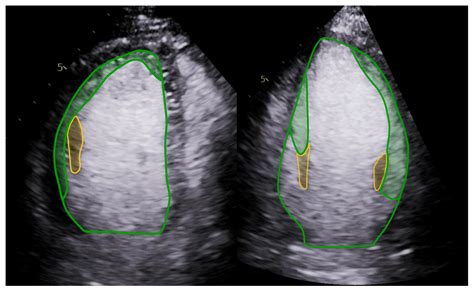

The primary purpose of adding a contrast agent during your scan is to improve the visibility of internal structures. Without contrast, some tissues may appear similar in density, making it difficult for a physician to identify subtle abnormalities. By using a contrast agent, the substance travels through your blood vessels and accumulates in areas of increased blood flow, such as tumors, areas of inflammation, or damaged blood vessels. This “enhancement” makes these areas appear brighter or more defined on the resulting images.

• Cardiovascular imaging: Doctors use it to visualize blood flow through heart chambers and vessels.